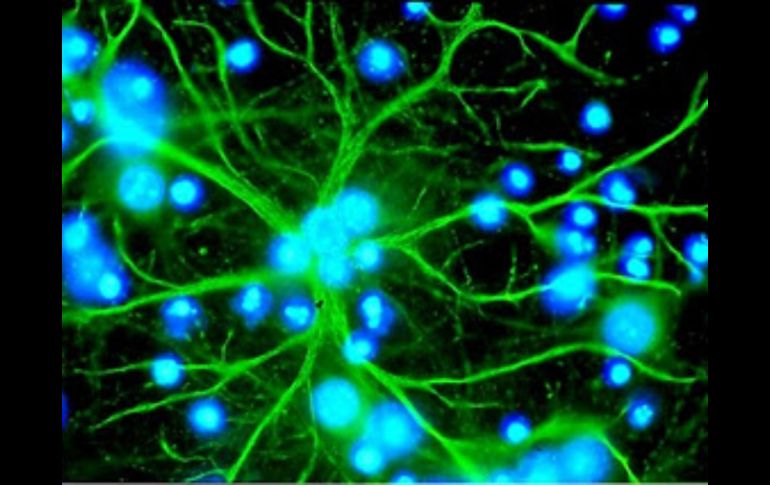

Tecnología | Los astrocitos son las células más abundantes del cerebro Descubren el papel 'clave' de los astrocitos en la formación del Alzheimer Hasta ahora se sabía que la inflamación del cerebro asociada a la enfermedad se desencadena por la acción de las células microgliales Por: EFE 25 de octubre de 2011 - 12:54 hs Desde que se descubrieron, los astrocitos se han considerado sostenes de la neurona. ESPECIAL / MADRID, ESPAÑA (25/OCT/2011).- Un equipo liderado por investigadores del Consejo Superior de Investigaciones Científicas (CSIC) de España ha descubierto que los astrocitos, las células más abundantes del cerebro, tienen un papel "clave" en el desarrollo del mal de Alzheimer. Hasta ahora se sabía que la inflamación del cerebro asociada a la enfermedad se desencadena por la acción de las células microgliales, encargadas de la defensa del sistema nervioso central. Sin embargo, esta investigación ha determinado que los astrocitos también intervienen activamente en la formación del Alzheimer porque en ellos transcurre "una fase esencial" del proceso inflamatorio. Mediante técnicas de ingeniería genética, los científicos han imitado la enfermedad en ratones y han observado cómo se produce la inflamación, un proceso relacionado con la producción de un tipo de proteínas citotóxicas -denominadas citoquinas-, que acaba siendo perjudicial para el cerebro a lo largo del tiempo. "Si no hay inflamación en los astrocitos, la enfermedad no se desarrolla", explica Ignacio Torres Alemán, investigador del CSIC en el Instituto Cajal y director del estudio, que aparece publicado en el último número de la revista Molecular Psychiatry. Desde que se descubrieron, los astrocitos se han considerado sostenes de la neurona. Sin embargo, "actualmente se cree que su papel es mucho más activo y que inciden directamente en la función cerebral. Además, su influencia en las enfermedades neurodegenerativas está tomando relevancia. Nuestras observaciones apoyan este papel central", señala el investigador. El trabajo abre la vía para diseñar tratamientos que consigan atacar la enfermedad, ya que los investigadores han corroborado la presencia de estos mismos procesos en cerebros humanos. "Los antiinflamatorios se han probado en enfermos sin efectos positivos. La razón no está clara, pero ahora sabemos que los fármacos deben luchar selectivamente contra la inflamación de estas células", destaca Torres Alemán. Temas Ciencia médica Enfermedades Cerebro Alzheimer Neurología Lee También Julieta Fierro será homenajeada en la FIL INAPAM: ¿Cómo solicitar un turno para consulta médica gratuita? Nobel de Química premia el desarrollo de estructuras metal-orgánicas Nobel de Física para Clarke, Devoret y Martinis por descubrimiento sobre fenómenos cuánticos Recibe las últimas noticias en tu e-mail Todo lo que necesitas saber para comenzar tu día Registrarse implica aceptar los Términos y Condiciones